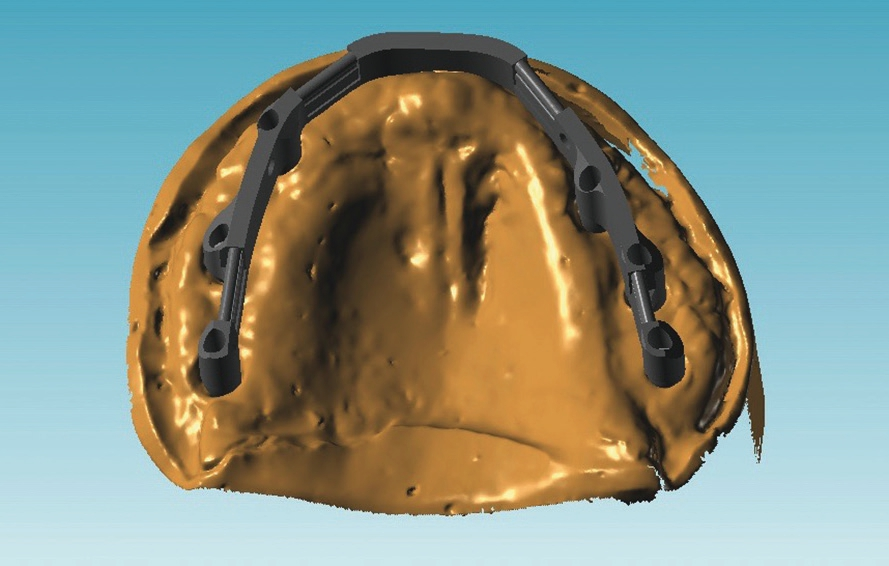

Wichtig sind bei dieser Art der Versorgung die exakte Planung der Behandlungsschritte und eine ideale Zusammenarbeit zwischen dem Implantologen, dem Prothetiker und dem Labor. Im vorliegenden Fall fiel die Wahl auf einen im CAD/CAM-Verfahren industriell gefrästen Steg, da dieser bei sorgfältiger Übertragung der Mundsituation auf die Arbeitsmodelle mittels Abformung und Bissregistrierung eine präzise Passung und einen spannungsfreien Sitz gewährleistet. Mit Hilfe der CAD/CAM-Technologie haben wir die Möglichkeit, dem Patienten eine äußerst präzise und langzeitstabile prothetische Lösung anzubieten und dennoch die Kosten in einem überschaubaren Rahmen zu halten.

Vor dem zweiten OP-Eingriff nach 4 Monaten wurde im Labor eine Bohrschablone angefertigt. Zudem wurde ein DVT angefertigt, um im Sinne eines Backward planning die ideale Implantatposition planen zu können. Bei Eröffnung des augmentierten Kieferbereiches zeigte sich im augmentierten Bereich eine gute Regeneration und Revaskularisierung des Knochens (Abb. 14 bis 17). Sechs Implantate konnten somit in den augmentierten Bereich (Astratech EV®, DENTSPLY Sirona, Mannheim) mit ausreichender Länge und Durchmesser in Form einer gleichmäßigen Pfeilerverteilung in den Kieferknochen Inseriert werden (Abb. 18).